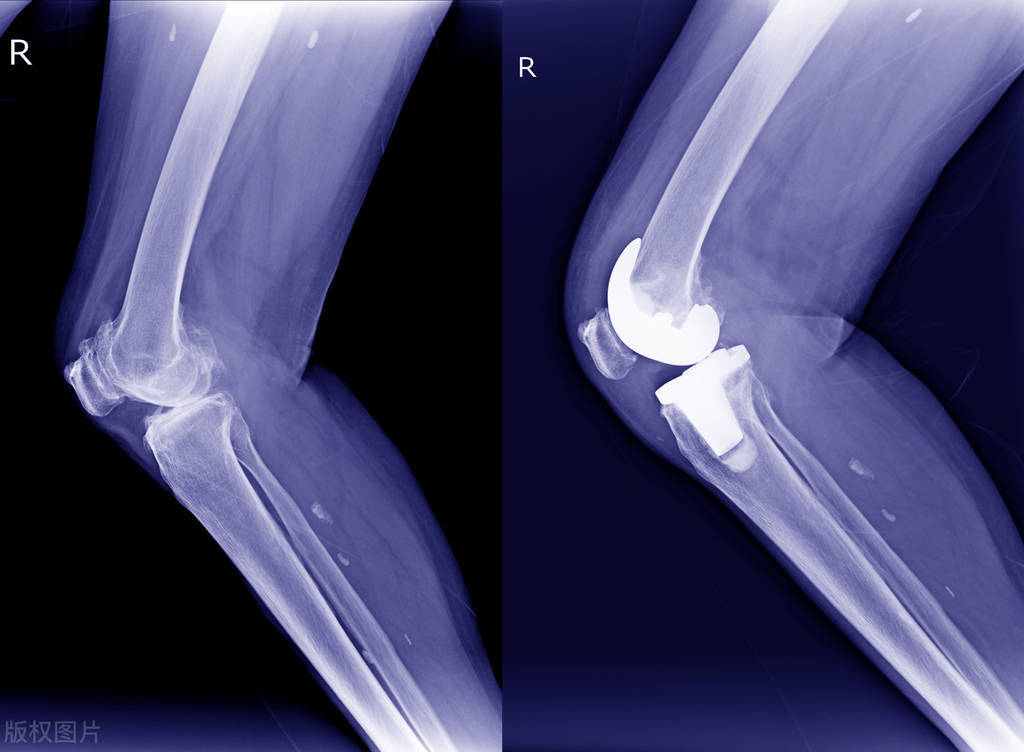

人工膝关节置换手术后,一个月时间里度日如年

人老先老腿。随着右膝关节的病变,我不得不接受人工关节置换手术。

我扪心自问,做这个膝关节置换后悔了吗?后悔真谈不上,原以为做了手术就是一劳永逸了,能过正常生活,正常走路了。但现实狠狠的打了我一个耳光。接下来的康复锻炼让你永生难忘。